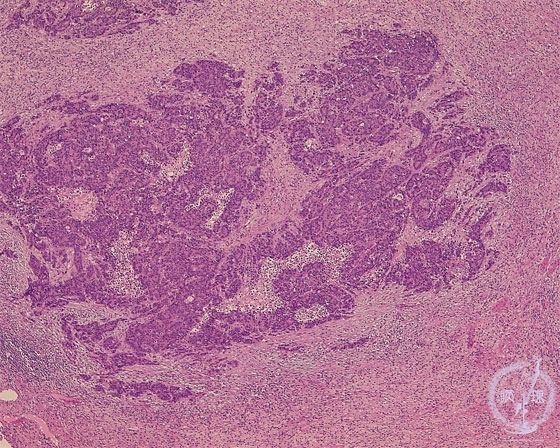

Microscopic view (HE stain, low power view): Small cell carcinoma of lung. The neoplastic cells are small with a high N/C ratio and they proliferate diffusely with no characteristic pattern.

Click the image to see the enlarged image.